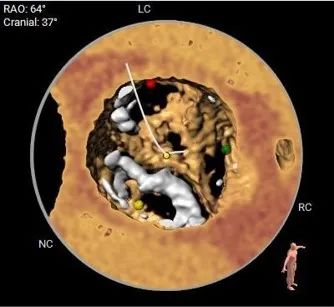

瓣上多平面分析

• 三叶式主动脉瓣,以风湿性改变为主,瓣叶显著增厚,R-L间纤维粘连,轻度钙化,钙化主要沿无冠窦瓣缘分布,LVOT直筒型对人工瓣膜的释放技巧有较高要求

• 左、右冠高度可,切线位测量,无冗长瓣叶,结合瓦氏窦、STJ 内径综合预估,冠脉阻塞风险适中

工作位多角度评估瓣膜形态,位置理想

超声多切面评估,瓣膜植入位置理想,血流动力学改善明显